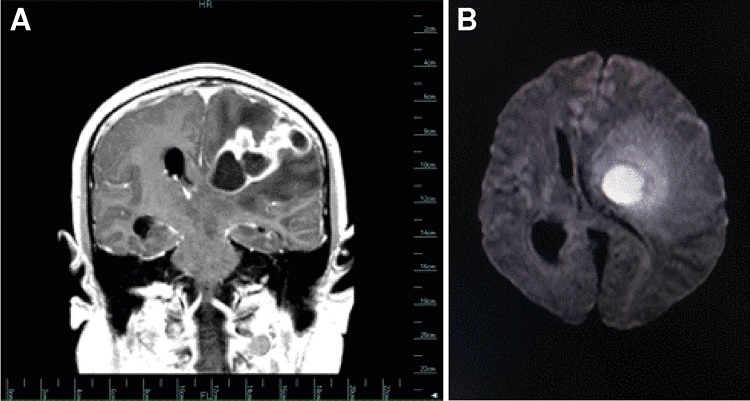

En la resonancia magnética cerebral se demostró una lesión intraaxial que ocupaba espacio, multiquística, compleja y de localización córtico-subcortical, en la la región fronto-temporo-parietal del hemisferio cerebral izquierdo, que comprometía la sustancia blanca profunda y el ganglio basal superior, con efecto compresivo y desplazamiento de los ventrículos ipsilaterales y herniación del cíngulo por debajo de la hoz del cerebro, característica de neoplasia o infección (figura 1).